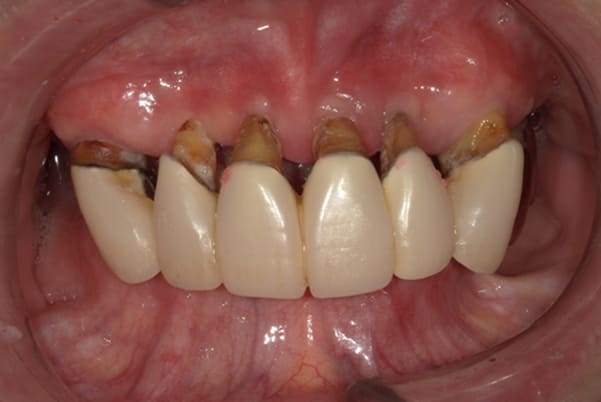

症例レポート[CASE.02]

入れ歯がカパカパして痛い、

歯がぐらぐらする

- 性別・年齢

- 男性(60代)

- 主訴

- 入れ歯がカパカパする、歯がぐらぐらして痛い、食いしばれない

- 治療

-

- 上顎精密総金属床総入れ歯

- 下顎精密金属床部分入れ歯

- ジルコニアクラウン4歯

- 治療期間

- 約3か月間

- 費用

- 上顎精密総金属床総入れ歯:55万円

- 下顎精密金属床部分入れ歯:55万円

(ミリング、ラベット加工込み) - ジルコニアクラウン:11万円×4歯

合計:154万円(税込)

上の前歯が重度歯周病により動揺し、残せない状態のため、入れ歯も動揺がありました。

ご自身の歯に負担の少ないバネ、また見た目も改善

バネをかける歯は繋げることで強度を増し、歯への負担を軽減し、歯の寿命を長くする設計へ。

バネがかかる歯の被せ物は、歯への負担を減らし、入れ歯が動きにくいようになる形態をあらかじめ付与することで、より入れ歯の機能が高まります。

治療を行う際、被せ物や入れ歯は、別々に考えるのではなく、一口腔単位としてお口全体のことを考え最良の治療計画を立てることが歯の寿命、機能効果を向上させるため、専門医としてこのことは常に心掛けて治療を行っています。

残りの歯に負担がかからないよう、被せ物と入れ歯の一体化を図った入れ歯

治療前は上下奥歯の入れ歯が削れていることで、かみ合わせが低くなり唇もつむった状態でした。

かみ合わせを適切な高さに戻したことで、本来の自然な口元へ。